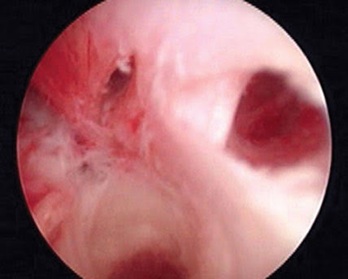

Hysteroscopy showing Adhesions in Left Cornua of Uterine Cavity (Asherman Syndrome). Left Ostia is obscured due to adhesions.

In a similar study Haemila et al., [10] in a study of females with premenopausal bleeding found that 3D TVS detected myomas in 14 (20%), polyps in 8 (11.43%), and endometrial mass in 1 while hysteroscopy detected myomas in 6 (8.57%), polyps in 11 (15.72%) and endometrial mass in 1 (1.43%). In contrast to the study above, we found that 3D TVS detected 20% abnormalities, out of which 15 (7.5%) were endometrial polyps, 6 (3%) were submucous myomas, 6 (3%) were septa, 1 (2%) were adhesions, and 5 (2.5%) was unicornuate uterus. While hysteroscopy detected 32.5% abnormalities, out of which 28 (14%) were polyps, 7 (3.5%) were submucous myomas, 5 (2.5%) were septa, 5 (2.5%) were adhesions and 5 (2.5%) were unicornuate uteruses. In our study, 3D-TVS failed to detect 13 (36.45%) cases with endometrial polyps, which were detected on hysteroscopy.